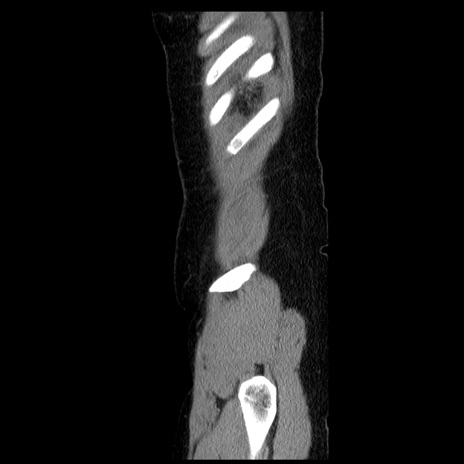

横断像

【症例】50歳代女性

【主訴】下腹部痛

【現病歴】本日朝より下痢2回あり。 昼食を食べた後、嘔吐3回、下腹部痛認め、症状軽快せず、当院救急搬送。

最終食事:本日昼(生ものなし)。 昨日の夜、刺身を食ぺたとのこと。周囲に同様の症状の者なし。普段、排便は毎日あるとのこと。

【既往歴】卵巣癌術後(8年前に当院で卵巣摘出)

【身体所見】 意識清明、腹部:平坦、腸蠕動音→、やや硬、下腹部自発痛・圧痛あり、反跳痛あり、筋性防御なし。

【データ】WBC 16000、CRP 0.01